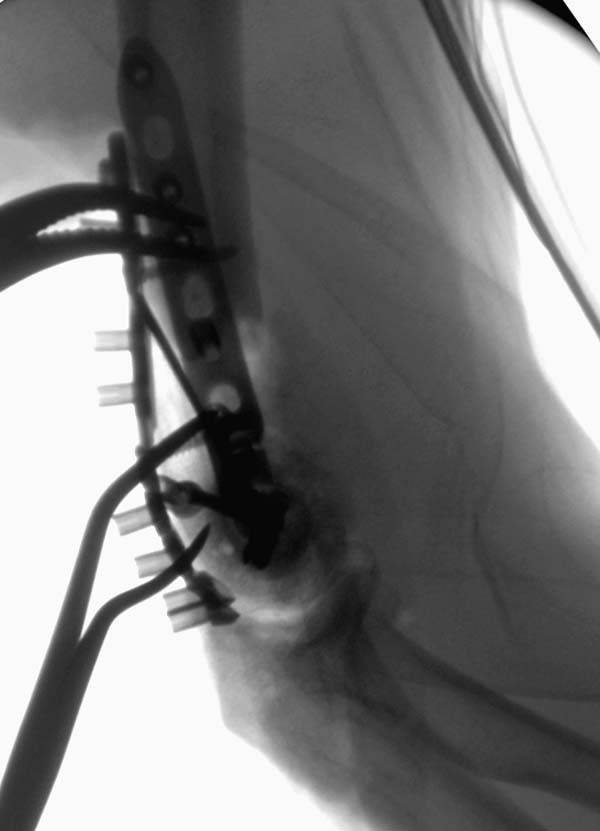

Примеры: первому более 15 лет фиксирован шурупом и tension band

technique, а второй перелом открытый больной 80 лет, после наружного

фиксатора в первом этапе и окончательная фиксация вторично. Третьий раз

внесуставная остеотомия...

Вложение не в текстовом формате было извлечено&hellip;

Имя     : 2-5 Distal Humerus CRM.JPG

Тип     : image/jpeg

Размер  : 30977 байтов

Описание: отсутствует

Url     : http://weborto.net:8080/pipermail/ortho/attachments/20130604/c45a379f/attachment-0007.jpeg

Имя     : 2-6 Distal Humerus CRM.JPG